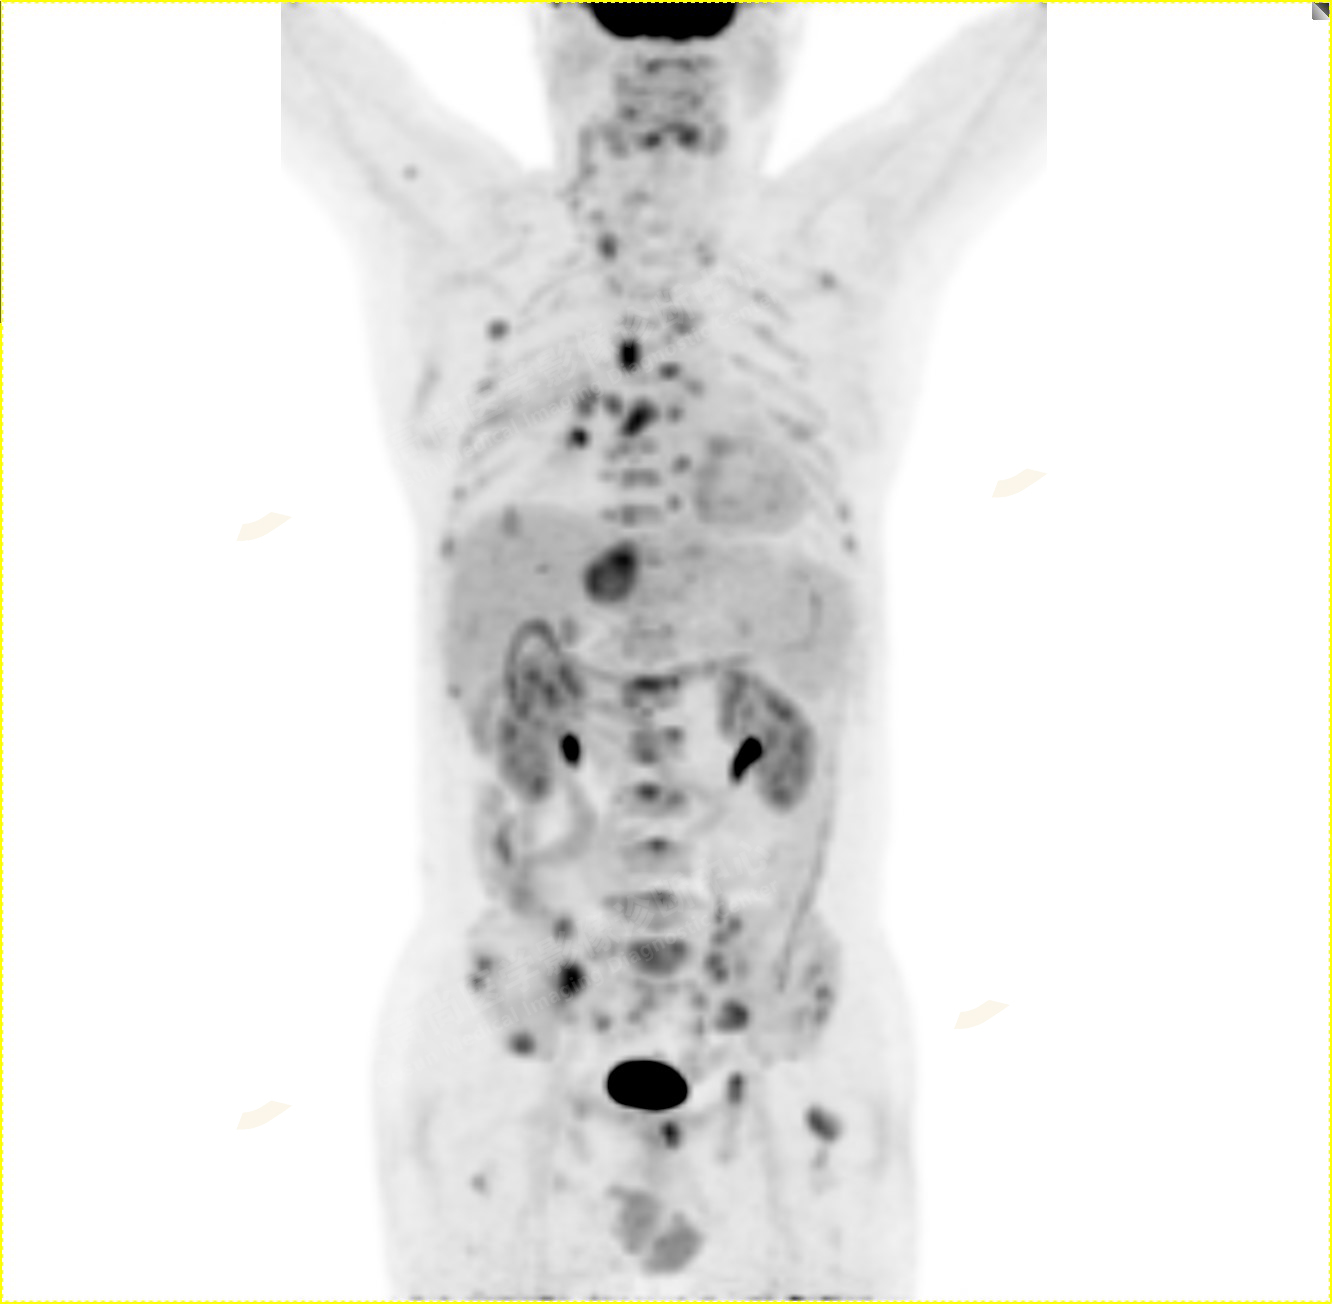

5.右側肱骨上段、左側肩胛骨、右側鎖骨胸骨端、胸骨、雙側多發(fā)肋骨、脊柱多發(fā)椎體及附件、雙側髂骨、雙側髖臼、雙側恥骨、雙側肱骨上段多發(fā)成骨性病變,呈不同程度FDG代謝異常增高,考慮為多發(fā)骨轉移瘤。

以上病變符合:T4N3M1c,ⅣB期(UICC/AJCC,2018年第8版肺癌TNM分期)。